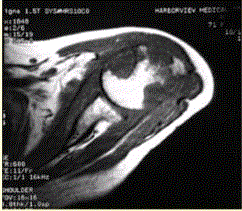

问题 患者女,71岁,双侧肩痛半年余。有较长SLE病史和激素用药史。行左肩X线平片、MR检查(下图)。 关于肩关节结核,下列描述正确的是

选项 A.肩关节结核病程进展快 B.肩关节为结核最好发部位 C.肩关节结核多为单纯性滑膜型结核 D.肩关节结核常常为双侧受累 E.侵犯滑膜、软骨和骨的结核为全关节结核

答案 E